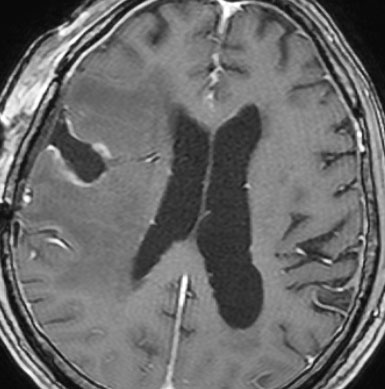

手術後の脳浮腫の改善

手術で放射線壊死巣を摘出してから1月半後のMRIです。放射線壊死が摘出されて,脳浮腫もかなり改善しました。同時に右麻痺もよくなってきました。

この例では,アバスチンを投与するという選択肢もあったのですが,医療費が高額で患者さんが経済的に耐えられません。